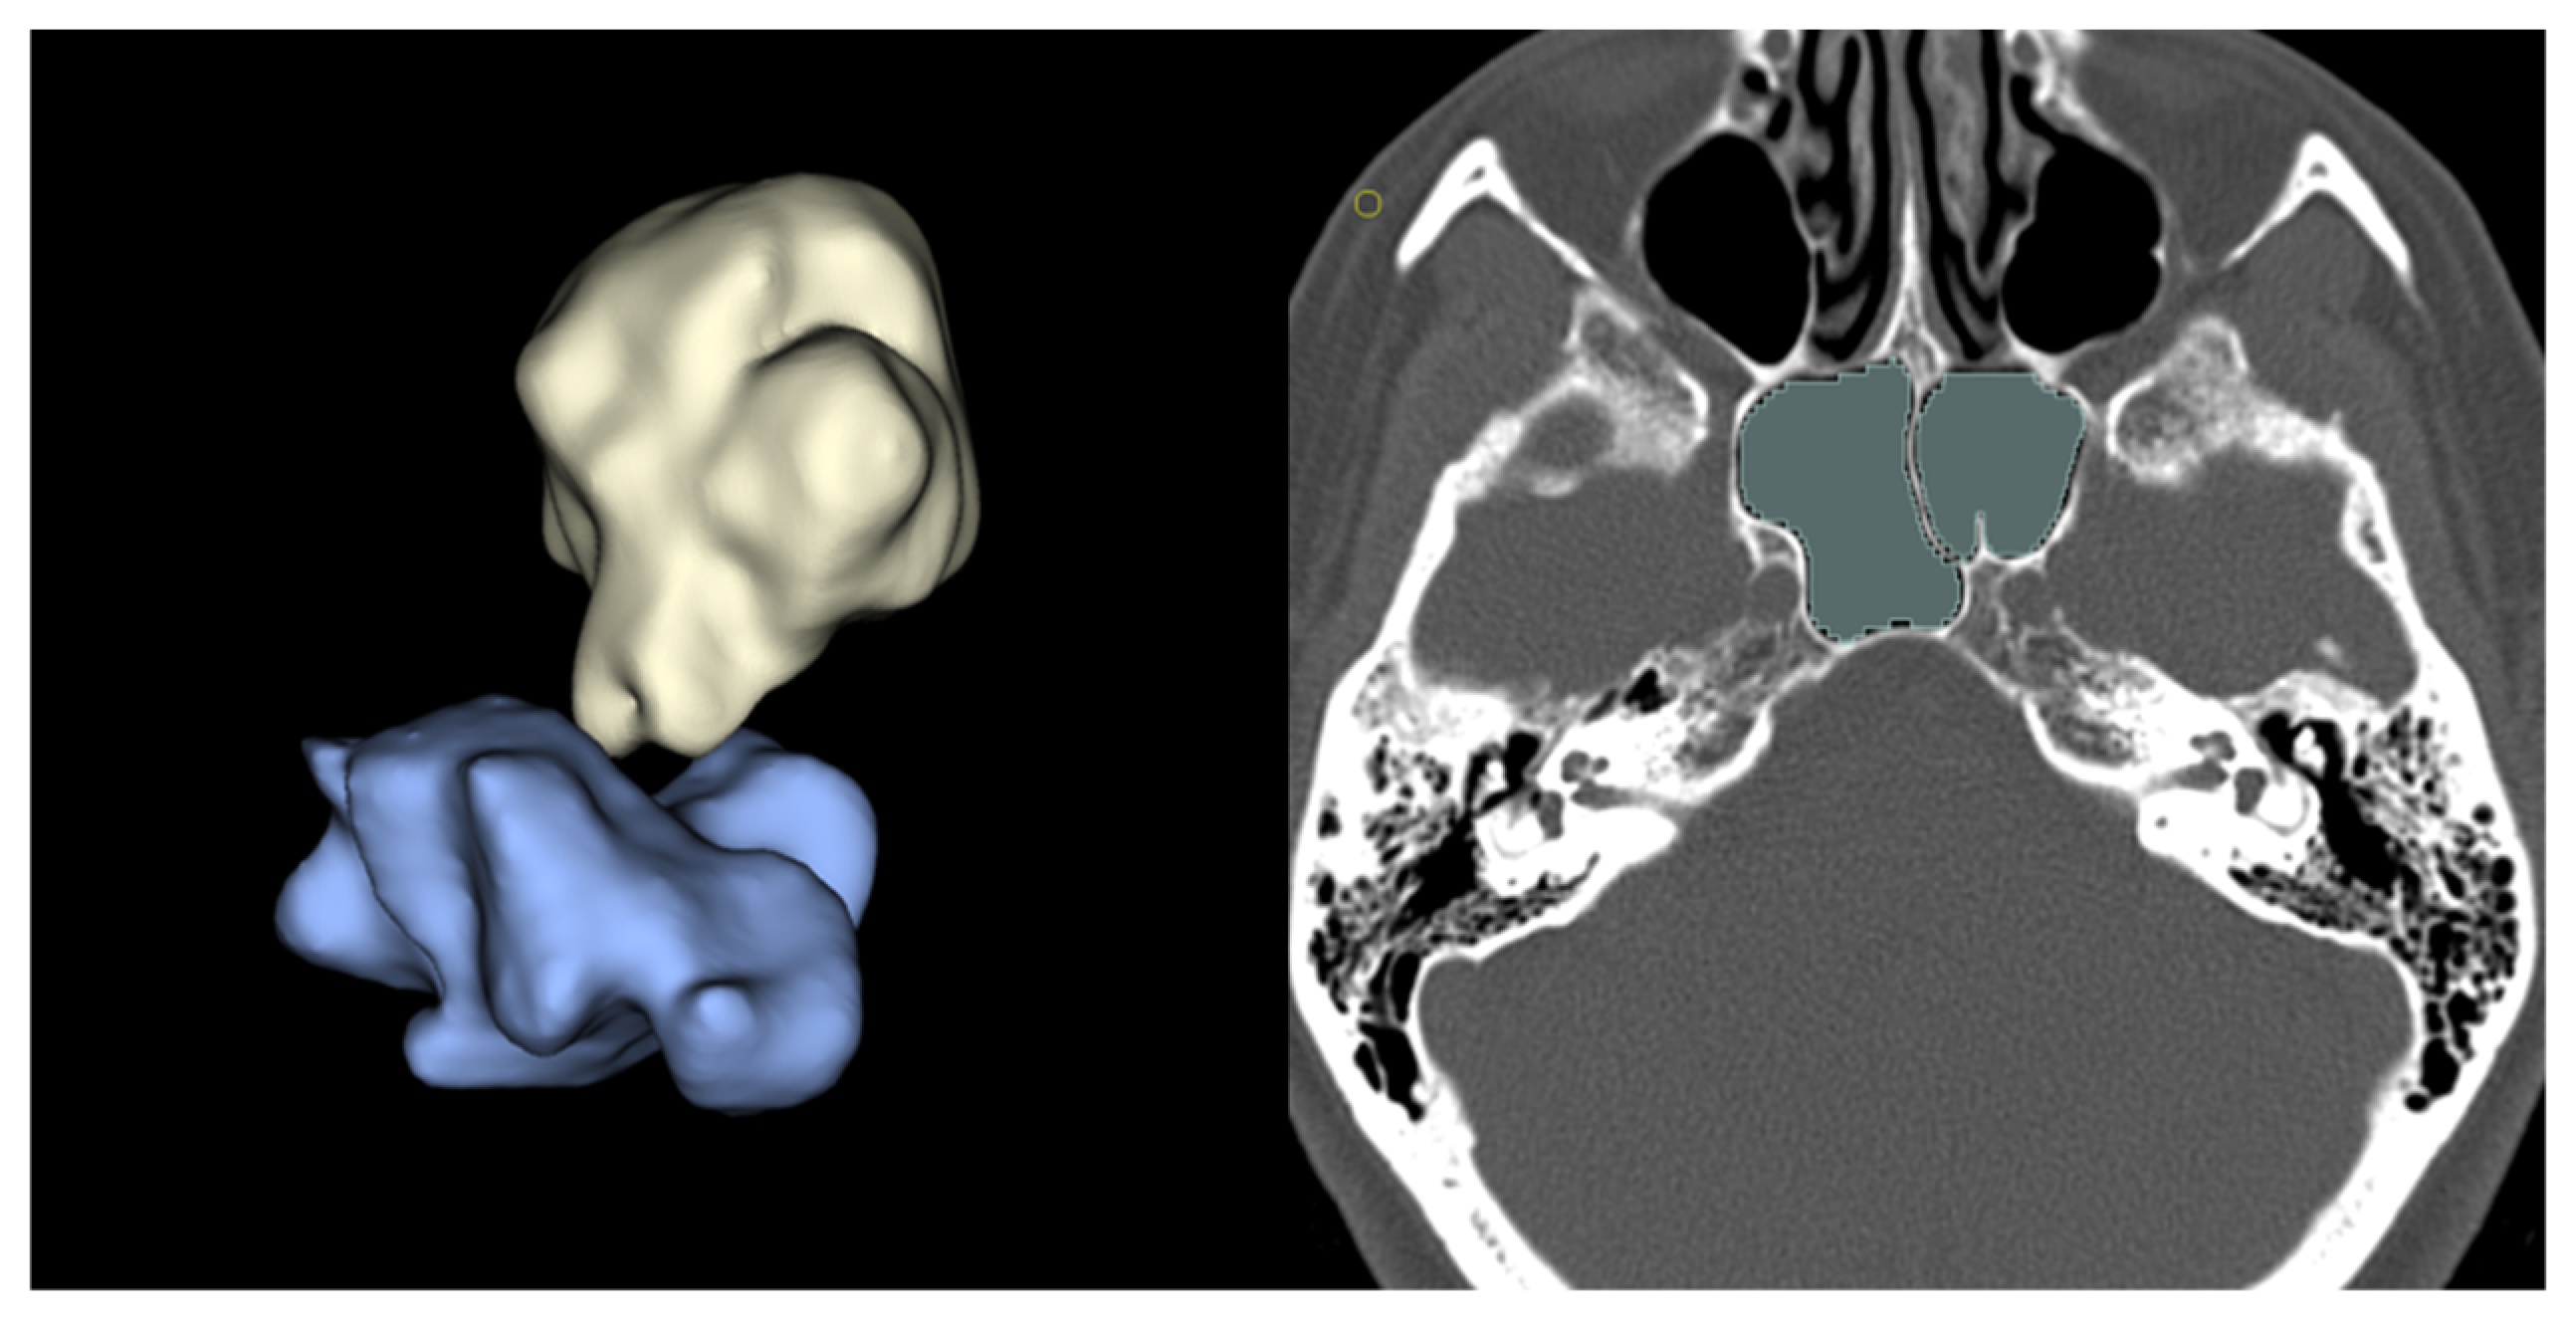

2.2.2. Imaging Study

- MRI imaging: Using a 3-Tesla Philips Achieva scanner (Philips Healthcare, Best, The Netherlands), 3D T1w (before and after gadolinium injection), FLAIR and T2w images were acquired.

- CT imaging: Acquired using a General Electric OPTIMA 660 scanner (GE Healthcare, Chicago, IL, USA), including a volumetric acquisition with bone window reconstruction.

2.3.1. Volumetric Analysis